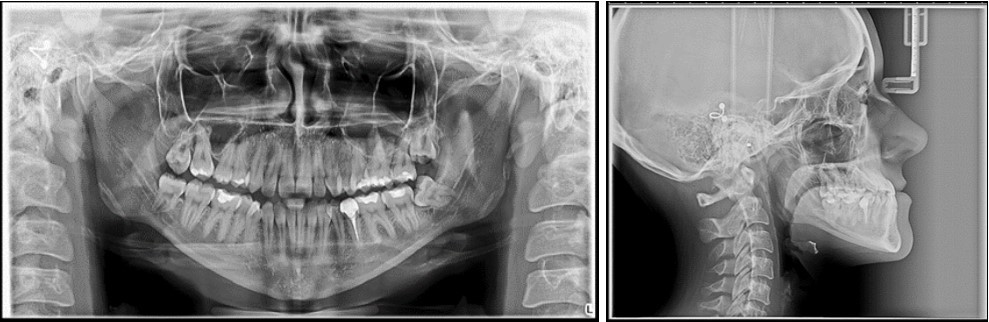

The panoramic radiograph examination showed impacted bilateral mandibular third molars, and one maxillary third molar.Cephalometric analysis disclosed a skeletal class III (ANB -5 degrees), with a retruded maxilla and a protruded mandible (SNA 78 degrees and SNB 83 degrees). The patient is a hyperdivergent type, with FMA 30 degrees and IMPA 77 degrees, which suggests retruded lower incisors. Examination of soft tissue on the profile radiograph shows a concave profile and a protruded lower lip. (Figure 3).

Figure 3.Initial panoramic and lateral cephalometric radiographs